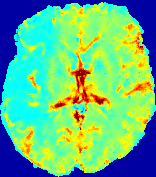

LesionRefer to captionRefer to captionRefer to captionRefer to captionRefer to captionRefer to caption𝐕rgbsubscript𝐕𝑟𝑔𝑏{\bf{V}}_{rgb}Refer to captionRefer to captionRefer to captionRefer to captionRefer to captionRefer to caption𝐕2subscriptnorm𝐕2{\|\bf{V}}\|_{2}Refer to captionRefer to captionRefer to captionRefer to captionRefer to captionRefer to captionRefer to caption3.53.53.52.82.82.82.12.12.11.41.41.40.70.70.70.00.00.0(mm/s)𝑚𝑚𝑠(mm/s)D𝐷DRefer to captionRefer to captionRefer to captionRefer to captionRefer to captionRefer to captionRefer to caption0.0200.0200.0200.0160.0160.0160.0120.0120.0120.0080.0080.0080.0040.0040.0040.0000.0000.000(mm2/s)𝑚superscript𝑚2𝑠(mm^{2}/s)Slice #1Slice #2Slice #3Slice #4Slice #5Slice #6

Figure 3: PIANO feature maps for one stroke patient, where the lesion is located in the left hemisphere. Top row: segmented stroke lesion region (white) on different slices, obtained from ISLES 2017. The corresponding slices for the PIANO feature maps are shown in the following rows.

For a better insight into an estimated velocity field 𝐕𝐕{\bf{V}} and diffusion field 𝐃𝐃{\bf{D}}, we compute the following maps: (1) 𝐕rgbsubscript𝐕𝑟𝑔𝑏{\bf{V}}_{rgb}: Color-coded orientation map of 𝐕=(Vx,Vy,Vz)T𝐕superscriptsuperscript𝑉𝑥superscript𝑉𝑦superscript𝑉𝑧𝑇{\bf{V}}=(V^{x},V^{y},V^{z})^{T}, obtained by normalizing 𝐕𝐕{\bf{V}} to unit length and mapping its 3 components to red, green, blue respectively; (2) 𝐕2subscriptnorm𝐕2\|{\bf{V}}\|_{2}: 222 norm of 𝐕𝐕{\bf{V}}; (3) D𝐷D: scalar field in Eq. 5.

Fig. 3 and Fig. 4 show the PIANO feature maps estimated from two ISLES 2017 patients: all are highly consistent with the lesion in both cases. Details of the blood flow trajectories are revealed in 𝐕rgbsubscript𝐕𝑟𝑔𝑏{\bf{V}}_{rgb} by the ridged patterns and the sharp changes of colors in the unaffected (right) hemisphere, while the flat patterns appearing within the lesion provide little directional information about the velocity and indicate low velocity magnitudes. Velocity magnitudes are more directly visualized via 𝐕2subscriptnorm𝐕2\|{\bf{V}}\|_{2}, from which one can easily locate the lesion where 𝐕2subscriptnorm𝐕2\|{\bf{V}}\|_{2} is low. D𝐷D also indicates lower diffusion values in the lesion, though with less contrast potentially due to the fact that it captures the accumulated effect of CA diffusion at the voxel-level.